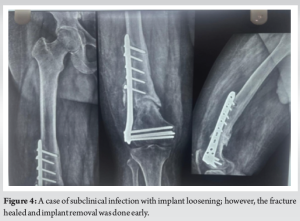

A total of 40 patients with distal femur fractures were included in the study, with a mean age of 57.4 years (range: 22–82 years), consisting of 26 females (65%) and 14 males (35%). The primary mechanisms of injury were motor vehicle accidents (55%) and falls (35%), while the remaining 10% were low-energy trauma in patients with osteoporosis. Fractures were classified using the AO/OTA system, with 25% being type 33-A, 40% type 33-B, and 35% type 33-C. The mean follow-up period was 12 months, during which outcomes such as union rates, complications, and functional recovery were evaluated. One of the cases of type 33-A3 (Fig. 1a) showed significant improvement in range of motion of the knee at 2–3 weeks post-operative (Fig. 1b and c), also followed by good radiological union at 12 weeks post-operative (Fig. 1d). [Fig. 1] One case of segmental comminuted SC fracture treated with MIPO, the proximal incision was extended a bit down to secure a large fragment extending to the diaphysis with a SS wire, however maintaining the principles of mipo fracture site not being disturbed. Post-operative X-ray shows better union at 3 months and 6 months follow-up, demonstrating the significance of MIPO in fracture healing in such high-grade fractures (Fig. 2). The study reported a union rate of 92.5%, with 37 out of 40 fractures successfully healing within a mean of 19.2 weeks (range: 16–24 weeks). Three patients (7.5%) experienced delayed union, though they ultimately achieved healing with conservative management.(Fig. 3). Complications occurred in 12.5% of cases (5/40), with three cases of malalignment (two of which were mild external rotational malalignment that did not require intervention, as the functional outcome was good), one case of screw breakage, and one subclinical infection. The infection was treated with antibiotics, while the screw breakage required constant vigilance to know if there is need for hardware exchange as the fracture was in good alignment and healing, with no cases of deep infection, implant failure, or nonunion. Radiographic analysis showed satisfactory alignment in 92.5% of cases, with only minor malalignment in three patients, none of which required surgical correction. (Fig. 4). Functional outcomes were assessed using the KSS, with almost 85% of patients achieving excellent or good results. Specifically, 62% had excellent outcomes, and 22% had good outcomes, indicating satisfactory knee function and mobility. Five patients (13%) reported f air results due to residual stiffness, and 1 patient (3%) experienced poor outcomes due to malalignment, which affected knee mobility. Overall, MIPO using locking plates proved to be a reliable and effective treatment method, with a high success rate and minimal need for secondary procedures.(Fig. 5).